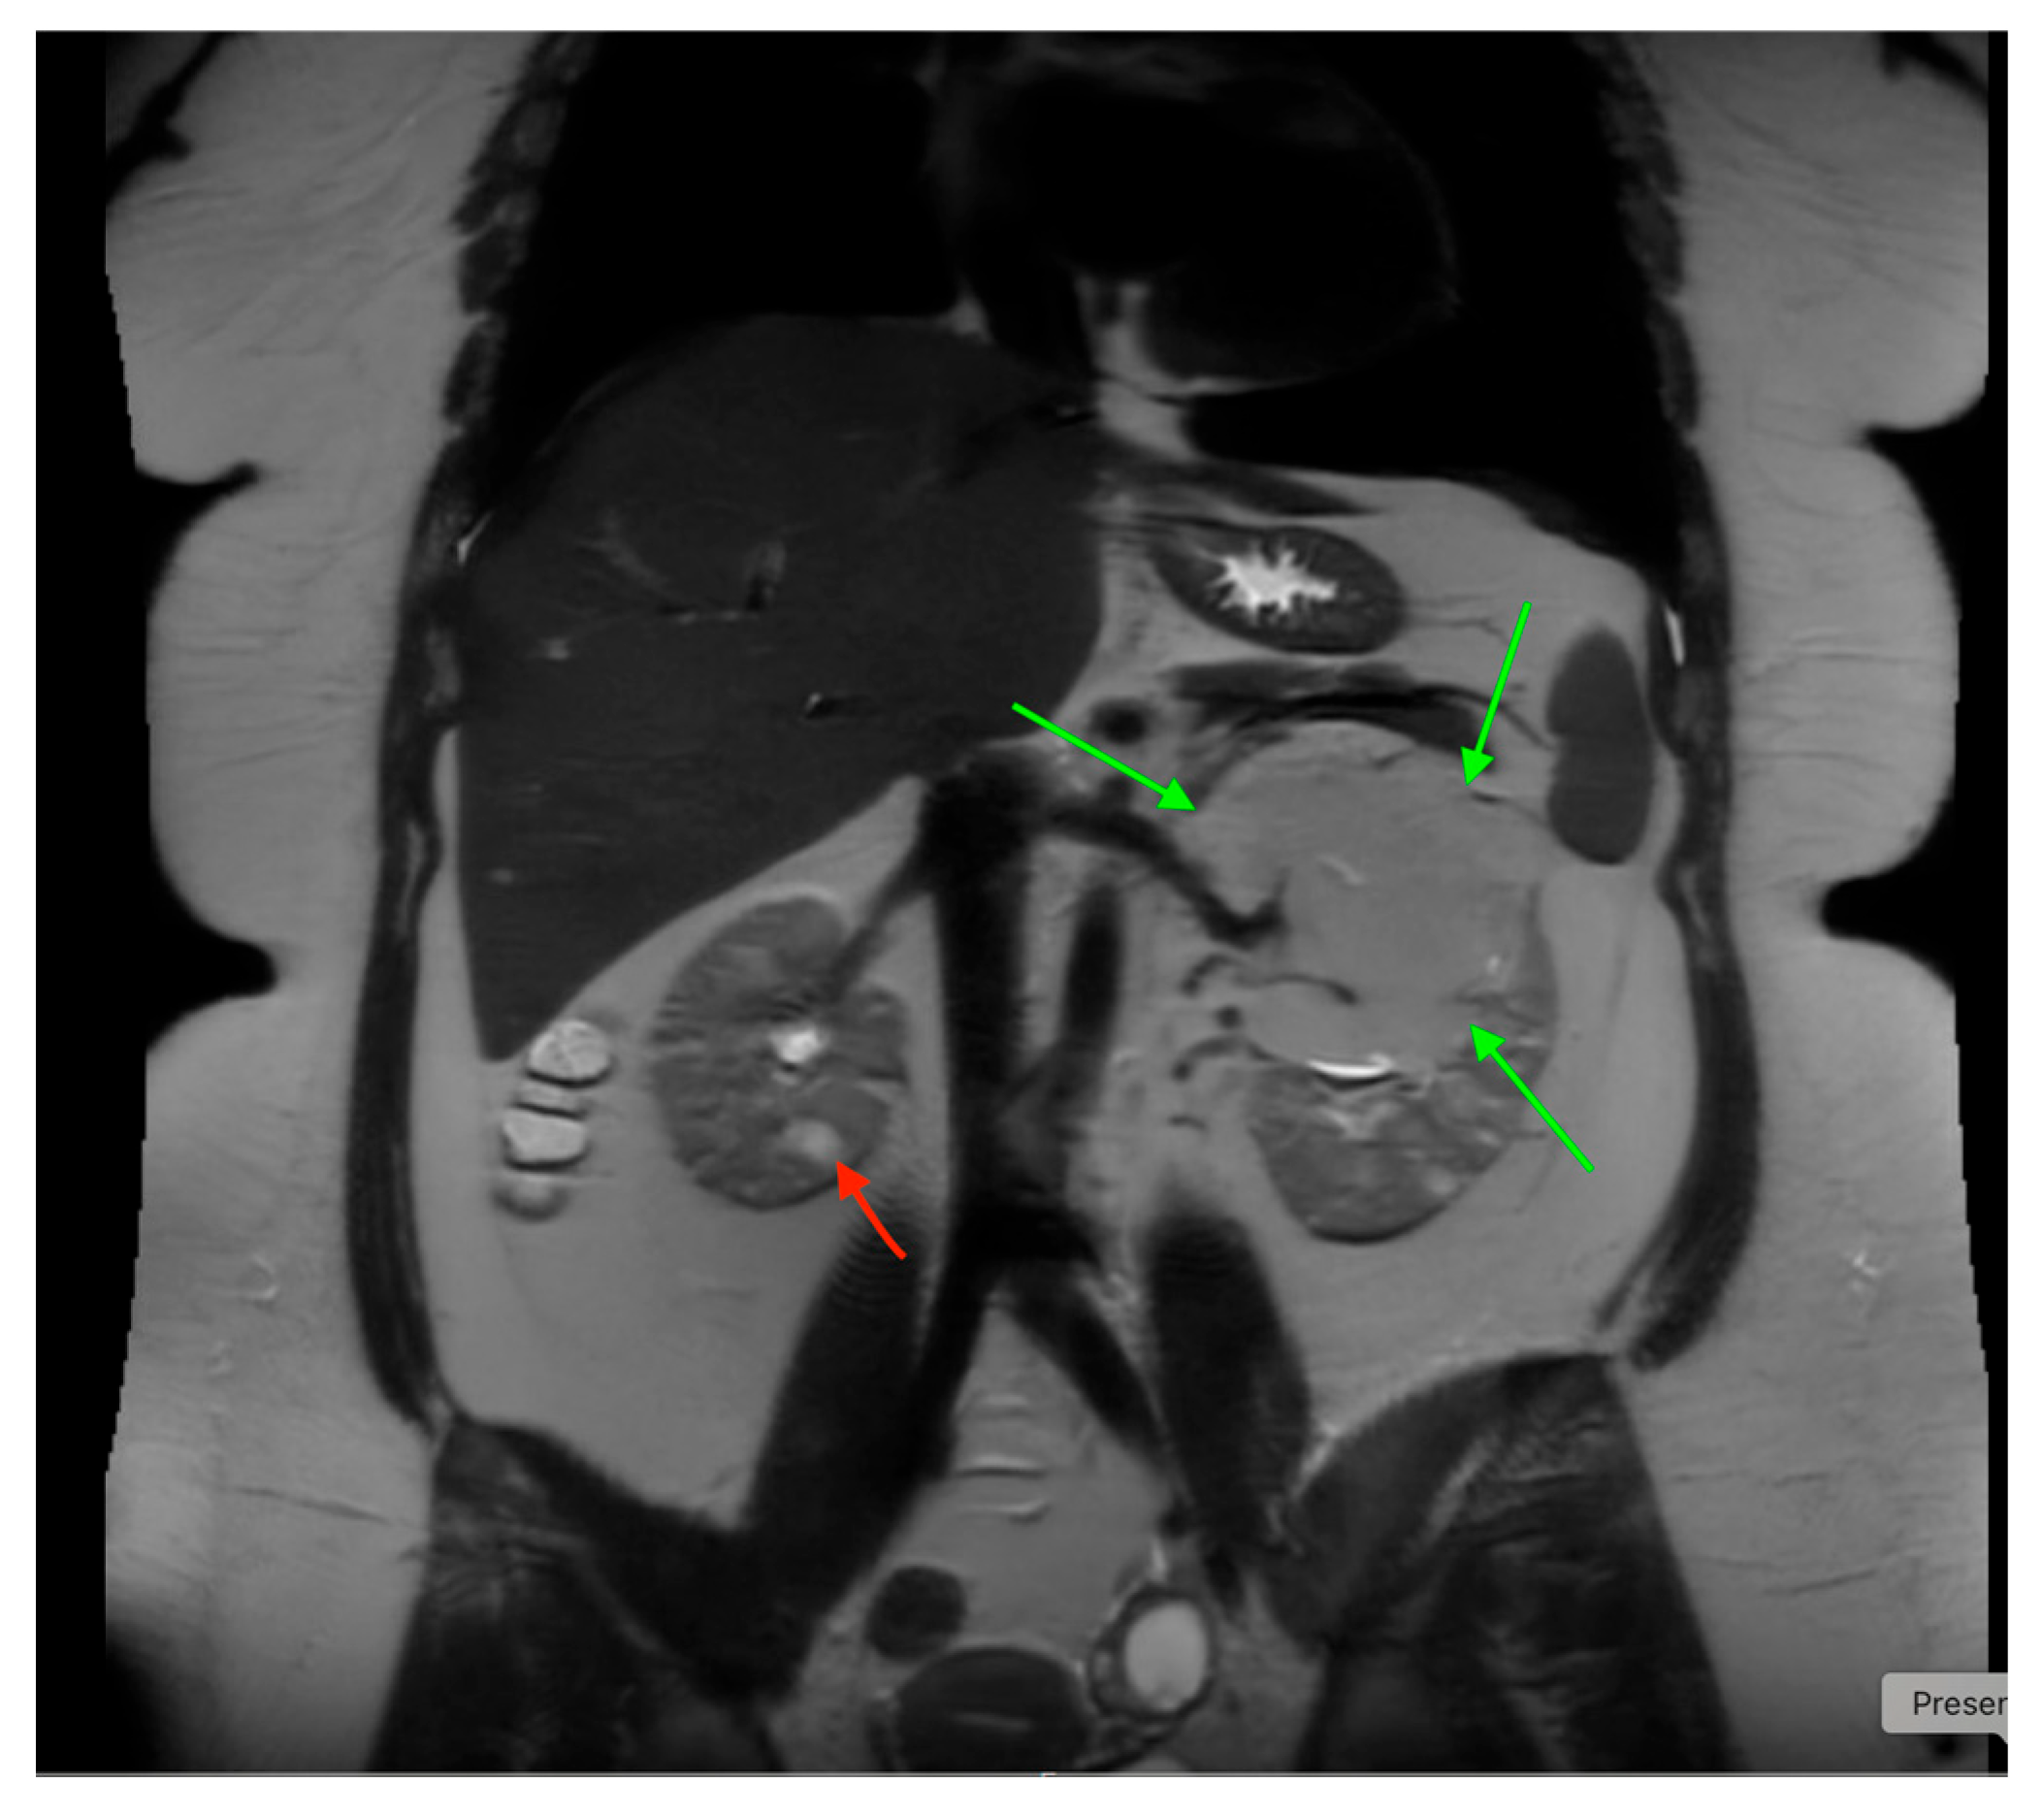

18. Tuberous Sclerosis

US, CT, and MRI are helpful in detecting angiomyolipomas, the most common renal lesions in tuberous sclerosis (TSC) (Figure 20). Some children with PKD1 and TSC2 mutations may develop severe cystic disease and are at risk for early renal failure (Figure 21) [72]. Children with TS should have a renal ultrasound at diagnosis and follow-up every 1–3 years [73]. Renal malignancies, such as malignant angiomyolipoma and renal cell carcinoma, are concerns in TSC and can occur in children [74,75]. Patients with rapidly changing lesions need more frequent imaging, and CT or MRI may be required to screen for malignant changes in severe kidney disease.

Figure 20. An abdominal MRI of an 18-year-old female with tuberous sclerosis reveals a large angiomyolipoma in the left kidney (marked by green arrows) and a smaller angiomyolipoma in the right kidney (marked by a red arrow).

Medicina 61 00696 g020

Figure 21. Abdominal MRI of a 16-year-old female with tuberous sclerosis, showing bilateral renal cysts (indicated by green arrows).

Medicina 61 00696 g021